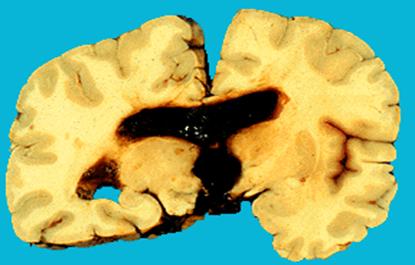

Рис.2.

Внутрижелудочковое кровоизлияние.